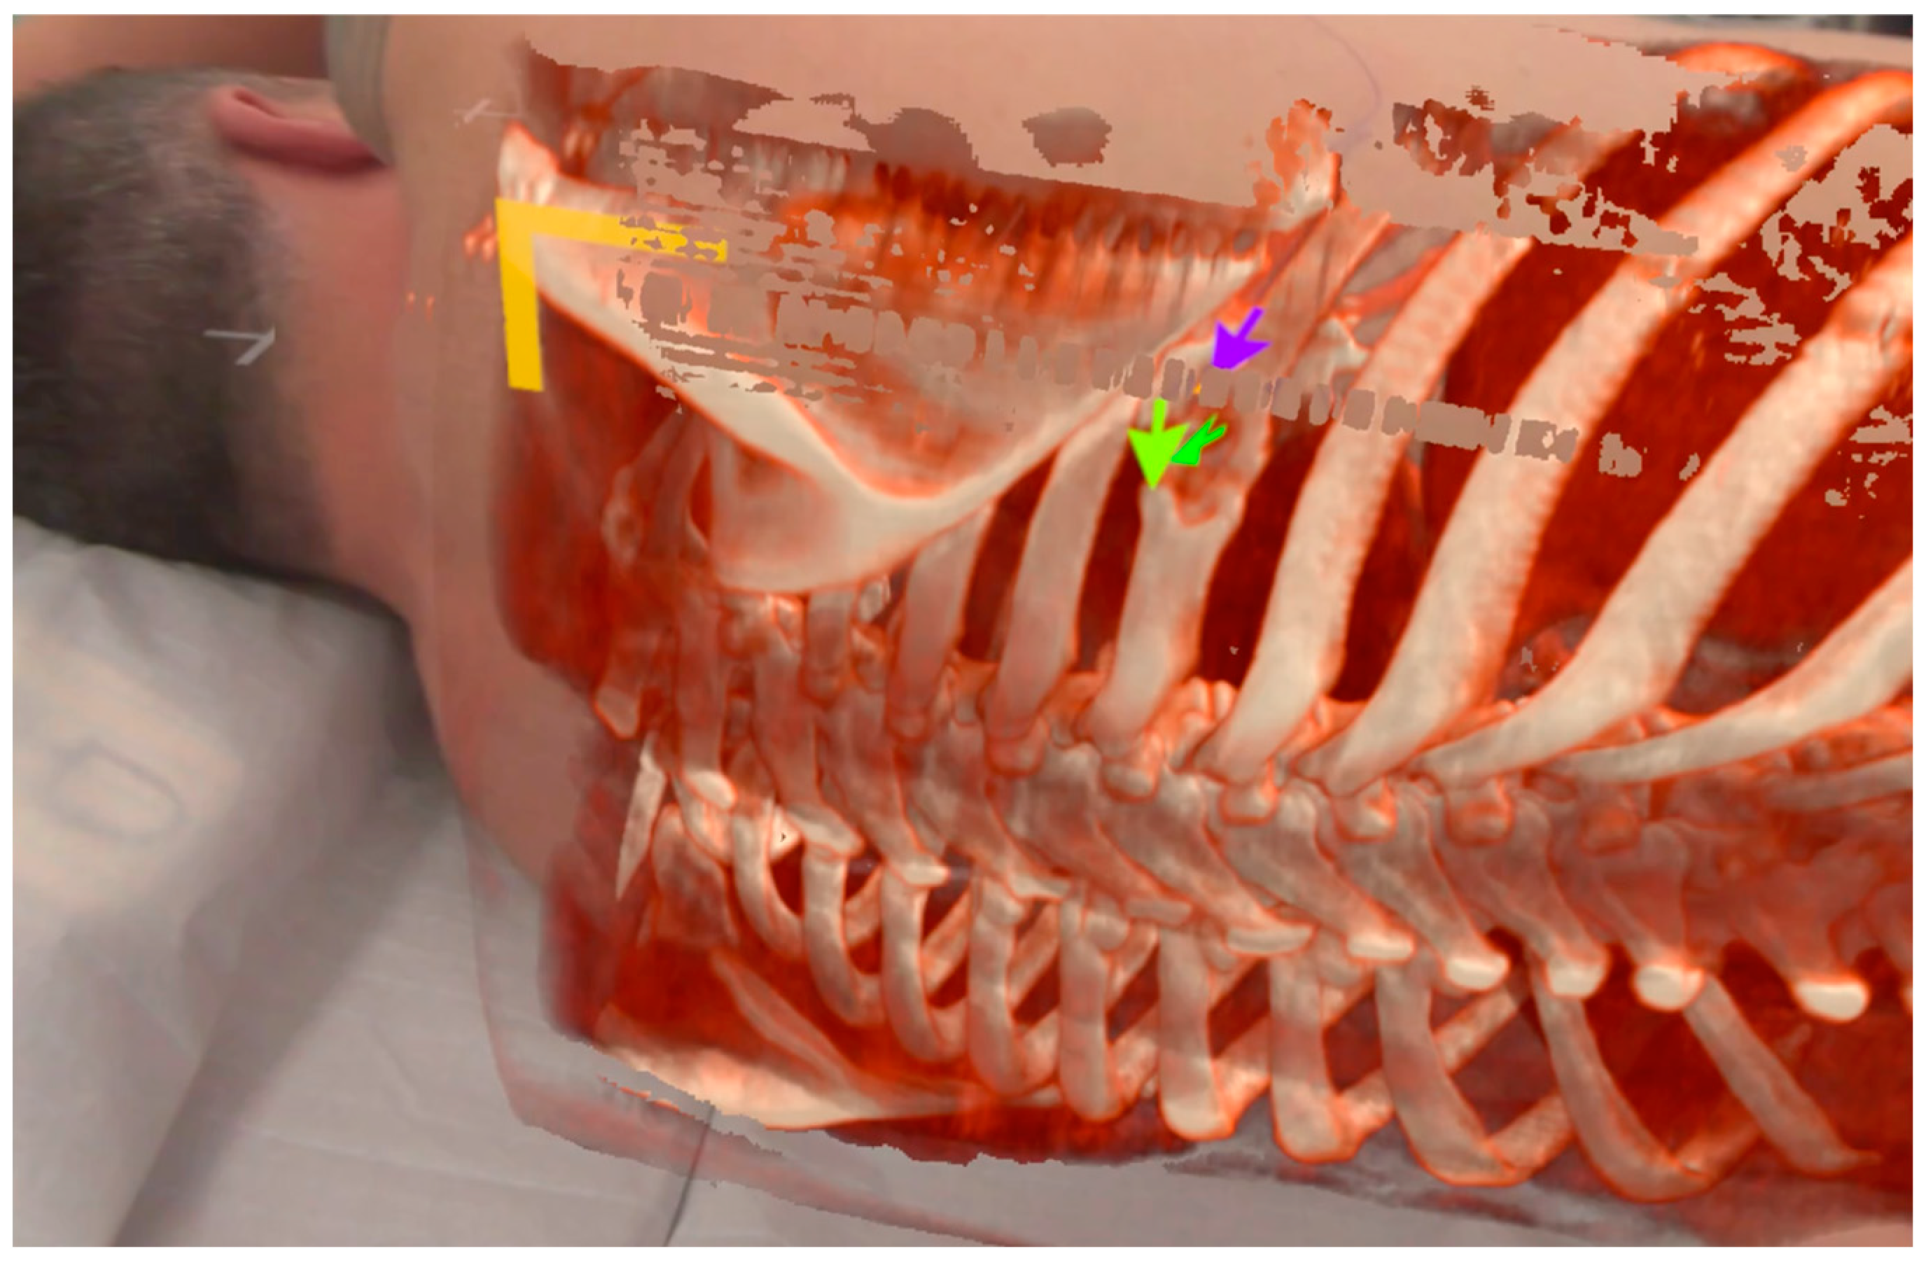

A third patient was diagnosed with an unclear suspected malignant lesion of the 7th rib of the right dorsal thorax with central osteolysis. During the XR assessment, the target was highlighted as displayed in

Figure 5. The rib lesion turned out to be benign in the histopathological findings after the partial rib resection was performed. It was most likely caused by an unrecognized fracture from the past with excessive callus formation.

During the examination of the first patient, a troubling issue was observed: depth perception became impeded due to the absence of superimposition of closer objects over more distant digital content. This issue particularly impacted perception during manual interaction with the patient. To ameliorate this, the adapted software version 0.10.0 was used for patients 2 and 3. The software utilized LiDAR sensor technology integrated within the Varjo XR-3. It was configured to overwrite digital content with a depth map of the environment within a 60 cm distance from the examiner’s position. The effect of this modification is clearly discernible in the ‘cutout’ of the examiner’s hand, as depicted in

Figure 5. LIDAR-based surface mapping caused the overwriting of the patient’s surface onto the surface of the holographic overlay. This created a phenomenon characterized by artifacts resembling ‘freckles’ upon the matching of the surfaces (within the range of 60 cm from the examiner). This distinctive occurrence proved to be helpful as an indicative marker for a good overlay positioning. It should be emphasized that the alignment was meticulously readjusted in every case until this phenomenon was consistently observed.